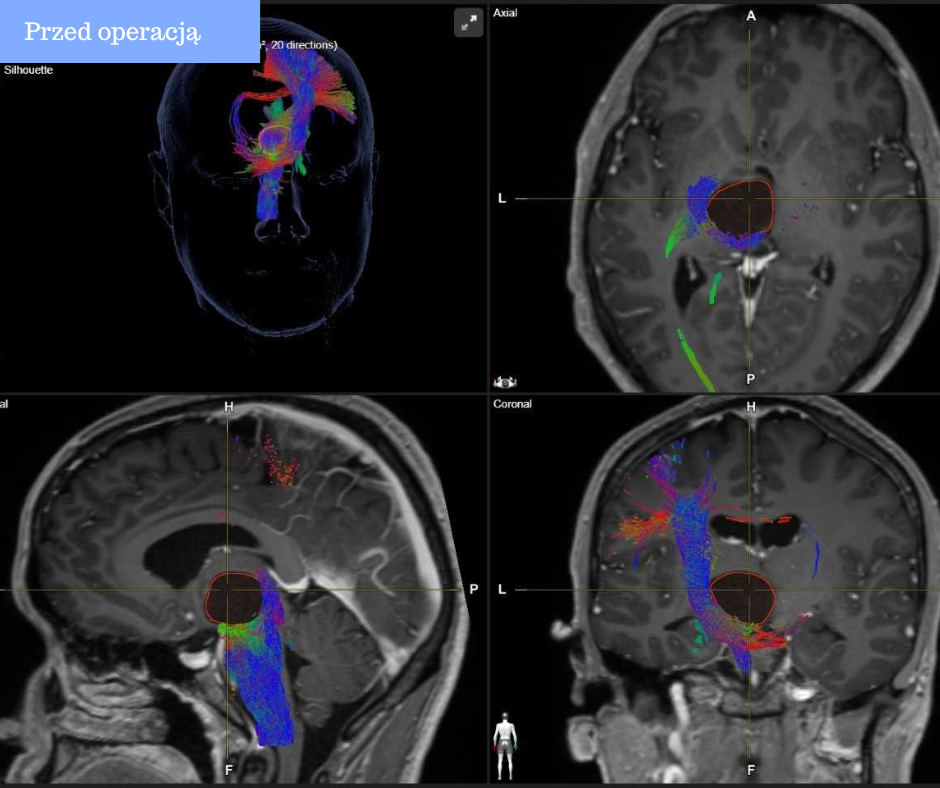

Nowoczesny sprzęt zakupiony w ramach projektu PL-UA, niestandardowe podejście i odważna decyzja neurochirurgów z Uniwersyteckiego Szpitala Klinicznego w Białymstoku (USK) pozwoliły uratować życie 30-letniego pacjenta. Innowacyjny sprzęt był kluczowym elementem przeprowadzenia tej wyjątkowo trudnej operacji.

Pan Adam w połowie 2025 r. zaczął mieć problemy z mówieniem. Potrafił odpowiadać na proste pytania „tak” lub „nie”, ale już skonstruowanie dłuższego zdania było wyzwaniem. Z czasem bliscy zauważyli, że zaczął pisać jak pierwszoklasista: wolno i niewyraźnie. Pojawił się też problem ze wzrokiem oraz niedowład ręki. Zwykłe odkręcenie butelki z wodą zrobiło się bardzo trudne. Po diagnostyce w jednym ze szpitali okazało się, że za te wszystkie dolegliwości odpowiada kilkucentymetrowa torbiel położona głęboko w mózgu. Lekarze zaproponowali bardzo obciążającą operację polegającą na otwarciu czaszki, wejściu do mózgu przez spoidło wielkie i usunięcie zmiany. Niestety operacja wiązała się z bardzo dużym uszkodzeniem mózgu, lekarze nie ukrywali, że po operacji mężczyzna może mieć problem z pamięcią czy nawet przestanie mówić.

Igłą w zmianę

Małżeństwo nie ustało jednak w poszukiwaniach innej drogi ratunku. Żona pana Adama trafiła w Internecie na informację o pacjencie, któremu białostoccy neurochirurdzy z Uniwersyteckiego Szpitala Klinicznego (USK) usunęli zmianę w mózgu przez oczodół. Wyczytała też, że białostocka Klinika Neurochirurgii specjalizuje się w małoinwazyjnych, endoskopowych operacjach mózgu. Postanowili zasięgnąć opinii w Białymstoku. Lekarze z USK zakwalifikowali pana Adama do zabiegu. Specjaliści zaczęli jednak szukać jeszcze mniej inwazyjnej drogi dotarcia do zmiany ponieważ obawiali się, że dotarcie endoskopem do tak głęboko położonej zmiany może wiązać się z ryzykiem powikłań neurologicznych.

Wymyśliliśmy, że dostaniemy się do zmiany igłą o średnicy około 2 mm, którą wykorzystujemy przy innych zabiegach tzw. DBS czyli głębokiej stymulacji mózgu i zdrenujemy tę zmianę.

– mówi dr Robert Chrzanowski, neurochirurg wykonujący zabieg.

Z badań tomografii wiedzieliśmy, że jest to torbiel z płynem o gęstości wody. I faktycznie udało nam się zdrenować zmianę. Ściągnęliśmy 11 cm sześciennych płynu.